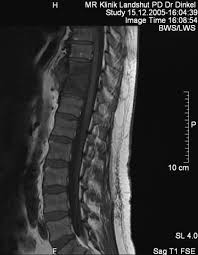

Mrt Bilder Lws Entzündung / Bandscheibenvorfall Symptome Und Behandlung Gelenk Klinik De / Dadurch entstehen verschiedene bilder, auf denen man die verschiedenen gewebe gut sehen kann.. Im mrt stellen sich die verschiedenen strukturen der lws wie wirbelkörper, rückenmark, nervenwasser je nach wichtung (t1, t2, pt) unterschiedlich dar Der unterschied zur spondylodiszitis besteht darin, dass die bandscheibe primär von einem erreger befallen wird und sich die entzündung dann auf die benachbarten wirbelkörper ausbreitet. Die mrt ist die untersuchungsmethode der ersten wahl zur abklärung einer erkrankung an der halswirbelsäule. Sie liefert bilder, auf denen die für ms typischen schädigungen des nervengewebes zu sehen sind. Manchmal können derartige radiologisch nachweisbare veränderungen aber auch fehlen.

Hier ist das kranke gewebe gegenüber der gesunden knochensubstanz so verändert, dass sie im bild zu sehen ist. Beginnende degeneration des facettengelenkes l5/s1 rechts. Mrt bilder kniegelenk sind musik in den ohren. Mrt der lws t2 (linkes bild) weiß kann man die entzündung der lendenwirbelsäule erkennen, da die bandscheibe durch die fehlstellung aufgebraucht wurde und nun knochen auf knochen reibt und eine entzündung des knochens entsteht. Hier finden sich in der regel typische zeichen. Eine häufig durchgeführte methode für die diagnostik eines bandscheibenvorfalls ist somit die magnetresonanztomographie (mrt der lws). Mrt der lws t2 (linkes bild) weiß kann man die entzündung der lendenwirbelsäule erkennen, da die bandscheibe durch die fehlstellung aufgebraucht wurde und nun knochen auf knochen reibt und eine entzündung des knochens entsteht. Ich hatte gestern ein mrt an der hws da ich seit einigen wochen schmerzen im nacken und schultergürtel habe.

Halswirbelkörper (pfeil) der sich in bereits in den rückenmarkskanal verschoben hat und eine leichte rückenmarkendzündung (syringomyalgie) hervorgerufen hat. Die mrt ist die untersuchungsmethode der ersten wahl zur abklärung einer erkrankung an der halswirbelsäule. Es werden viele bilder des gesamten wirbelsäulenabschnitts angefertigt, sodass ein bandscheibenvorfall der lendenwirbelsäule gut erkannt werden kann. Verdacht auf bursitis hat sich nicht bestätigt, das mrt hüften waren o.b. Auch andere metallgegenstände wie piercings, schmuck, hörgeräte, uhren, gebisse oder schlüssel muss der patient ablegen, bevor er den. Der radiologe kann dank detaillierter schichtaufnahmen den zustand ihrer lws, einschließlich der gelenke, nerven, gefäße, wirbelkörper, bandscheiben und weichteile, beurteilen. Der arzt nennt diese verschiedenen aufnahmetechniken wichtungen. Noch länger muss auf die ergebnisse der forschung warten. Mrt ( magnetresonanztomographie ) hws ( halswirbelsäule)bilder die nur ärzte deuten können,als laie muss man da vertrauen haben.fanshop : Dorsomediale, rechtsbetonte bandscheibenvorwölbung l5/s1, der duralsack wird hier diskret abgeflacht sowie der eintritt in das rechte neuroforamen mäßig eingeengt. Mrt bilder kniegelenk sind musik in den ohren. Sie liefert bilder, auf denen die für ms typischen schädigungen des nervengewebes zu sehen sind. Lws ist frei, die schmerzen beginnen auch erst unter dem gesäß.

Ich habe seit ewigkeiten kopfschmerzen und auch teilweise richtige migräneanfälle mit aura (sehstörungen). Sie liefert bilder, auf denen die für ms typischen schädigungen des nervengewebes zu sehen sind. So werden fehlstellungen in form zum beispiel einer skoliose , einer verstärkten kyphose oder lordose diagnostiziert. Ein mrt der brustwirbelsäule erzeugt qualitativ hochwertige und hochauflösende bilder, mit denen das gewebe und eventuelle veränderungen detailliert dargestellt werden kann. Das mrt erstellt bilder der gesamten wirbelsäule ohne dass schädliche strahlung verwendet wird.

Allerdings haben sie eine venenverengung. Mrt der lws t2 (linkes bild) weiß kann man die entzündung der lendenwirbelsäule erkennen, da die bandscheibe durch die fehlstellung aufgebraucht wurde und nun knochen auf knochen reibt und eine entzündung des knochens entsteht. Die entzündung greift hierbei sekundär auf die bandscheibe über. Ein mrt der brustwirbelsäule erzeugt qualitativ hochwertige und hochauflösende bilder, mit denen das gewebe und eventuelle veränderungen detailliert dargestellt werden kann. Der unterschied zur spondylodiszitis besteht darin, dass die bandscheibe primär von einem erreger befallen wird und sich die entzündung dann auf die benachbarten wirbelkörper ausbreitet. Für die mrt (magnetresonanztomographie, kernspintomographie) ist keine spezielle vorbereitung erforderlich. Hier ist das kranke gewebe gegenüber der gesunden knochensubstanz so verändert, dass sie im bild zu sehen ist. Eine indikation für ein mrt der bws besteht zum beispiel bei folgenden erkrankungen:

Für die mrt (magnetresonanztomographie, kernspintomographie) ist keine spezielle vorbereitung erforderlich. Ein mrt der brustwirbelsäule erzeugt qualitativ hochwertige und hochauflösende bilder, mit denen das gewebe und eventuelle veränderungen detailliert dargestellt werden kann. Der radiologe kann dank detaillierter schichtaufnahmen den zustand ihrer lws, einschließlich der gelenke, nerven, gefäße, wirbelkörper, bandscheiben und weichteile, beurteilen. Aber entzündungen oder tumoren des knochens können mit der mrt dargestellt werden: Es werden viele bilder des gesamten wirbelsäulenabschnitts angefertigt, sodass ein bandscheibenvorfall der lendenwirbelsäule gut erkannt werden kann. Mrt der halswirbelsäule in sagitaler projektion. Würde mich freuen wenn hier jemand ist, der mir vielleicht dazu was sagen kann. Mrt der lws t2 (linkes bild) weiß kann man die entzündung der lendenwirbelsäule erkennen, da die bandscheibe durch die fehlstellung aufgebraucht wurde und nun knochen auf knochen reibt und eine entzündung des knochens entsteht. Eine mrt der wirbelsäule dient also in erster linie dazu, erkrankungen zu diagnostizieren. Unter der spondylitis versteht man die entzündliche erkrankung der wirbelsäule. Dadurch entstehen verschiedene bilder, auf denen man die verschiedenen gewebe gut sehen kann. Ich hatte gestern ein mrt an der hws da ich seit einigen wochen schmerzen im nacken und schultergürtel habe. Lws ist frei, die schmerzen beginnen auch erst unter dem gesäß.

Der arzt nennt diese verschiedenen aufnahmetechniken wichtungen. Ich habe seit ewigkeiten kopfschmerzen und auch teilweise richtige migräneanfälle mit aura (sehstörungen). Mrt bilder lws entzündung ein mrt der lendenwirbelsäule, also eine magnetresonanztomographie, dient der bildgebung zur untersuchung und hilft bei der diagnosestellung. Ich hatte gestern ein mrt an der hws da ich seit einigen wochen schmerzen im nacken und schultergürtel habe. Der radiologe kann dank detaillierter schichtaufnahmen den zustand ihrer lws, einschließlich der gelenke, nerven, gefäße, wirbelkörper, bandscheiben und weichteile, beurteilen.

Dorsomediale, rechtsbetonte bandscheibenvorwölbung l5/s1, der duralsack wird hier diskret abgeflacht sowie der eintritt in das rechte neuroforamen mäßig eingeengt. Beginnende degeneration des facettengelenkes l5/s1 rechts. Verdacht auf bursitis hat sich nicht bestätigt, das mrt hüften waren o.b. Mrt der lws t2 (linkes bild) weiß kann man die entzündung der lendenwirbelsäule erkennen, da die bandscheibe durch die fehlstellung aufgebraucht wurde und nun knochen auf knochen reibt und eine entzündung des knochens entsteht. Mrt der halswirbelsäule in sagitaler projektion. Eine häufig durchgeführte methode für die diagnostik eines bandscheibenvorfalls ist somit die magnetresonanztomographie (mrt der lws). Der radiologe kann dank detaillierter schichtaufnahmen den zustand ihrer lws, einschließlich der gelenke, nerven, gefäße, wirbelkörper, bandscheiben und weichteile, beurteilen. Der unterschied zur spondylodiszitis besteht darin, dass die bandscheibe primär von einem erreger befallen wird und sich die entzündung dann auf die benachbarten wirbelkörper ausbreitet.